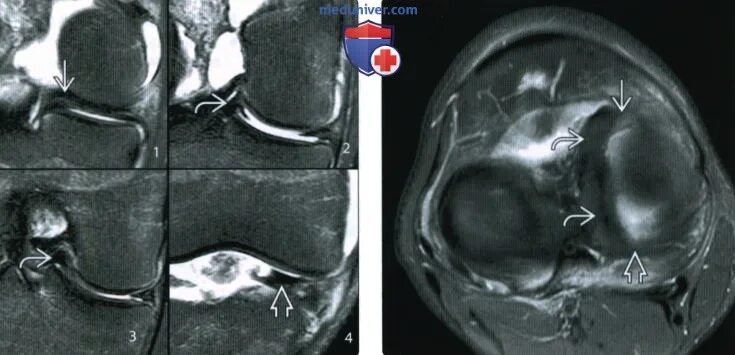

Дегенеративные изменения мениска по stoller